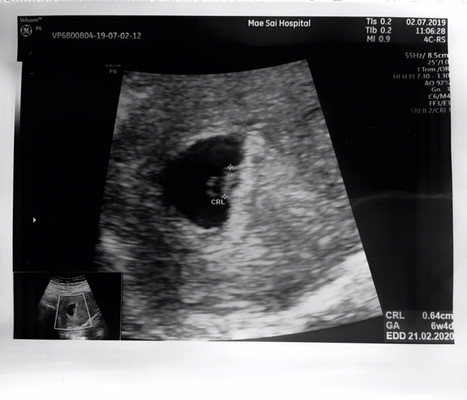

เพิ่ง 6w4d แต่น้องมีหัวใจแล้วเต้นแรงมากๆ ขนาดท้องสองนะคะ รู้สึกตื่นเต้นมากๆน้องกำลังตัวเล็กเลย พอได้ยินเสียงหัวใจรู้สึกตื้นตันใจบอกไม่ถูก ใครมีรูปอัตราซาวตอนน้องเล็กๆเอามาโชว์กันหน่อยค่า